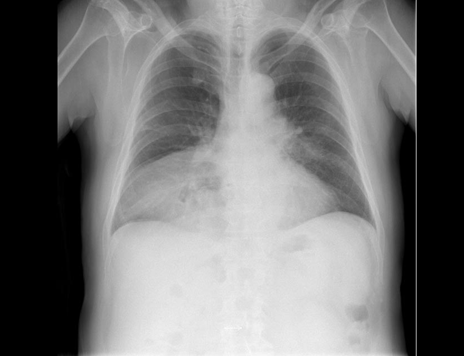

A 64-year-old male presented to our facility emergency department with the complaints of shortness of breath and abdominal pain. According to the assessment, chronical reactive changes such as chronical bronchitis were determined in the thoracic computed tomography (CT) and Morgagni hernia was in the abdominal CT scan. The patient was hospitalized in the general surgery service and taken to the operation for hernia mesh repair. The patient was considered to have American Society of Anesthesiologists (ASA) I risk status in preoperative assessment and had no abnormal finding other than diaphragmatic hernia on chest radiograph (Figure 1). Laboratory tests and serum sodium (Na+) concentration (142 mEq/L [142 mmol/L]) were found to be within normal range. The patient underwent hernia repair under general anesthesia; then, he was transferred to ward with Aldrete score of 9-10 after uneventful recovery period [3].

Figure 1: Preoperative lung image: Morgagni hernia, non-specific chronical bronchitis; bronchial wall thickening with increased bronchovascular markings.